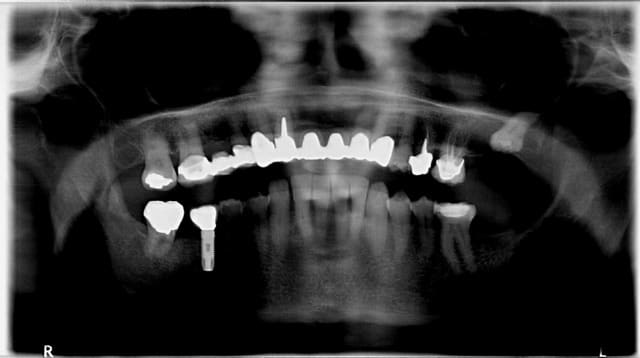

Je reçois ce matin ce mail plutôt désagréable, intitulé "votre devis hors norme", suite à une consultation en juillet pour un abcès sur la 12 (je joins les radios).

Le choix thérapeutique dépend de la balance bénéfice/risque. Pour moi la racine de la 12 n'est pas conservable (et donc le bridge non plus) car la racine est très courte et le tenon est très long. La résection apicale raccourcit encore la racine, et raccourcit d'autant la durée de vie de cette racine. J'ai donc écarté ce choix thérapeutique car il s'agissait pour moi de reculer pour mieux sauter. Mais peut-être me suis-je trompé, après tout je ne suis pas encore un chirurgien dentiste de renom. Seul le temps pourra dire si j'avais tord ou raison.